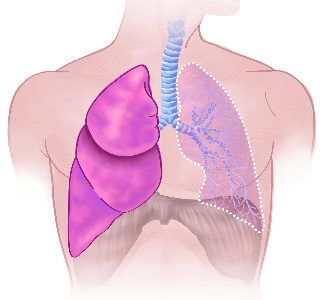

Detailreiche Fotografien aus der medizinischen Praxis ergänzen die Texte; moderne, genaue,

wissenschaftliche Zeichnungen geben Einblick in die Anatomie und die Funktion der Lunge und

anderer Organe.